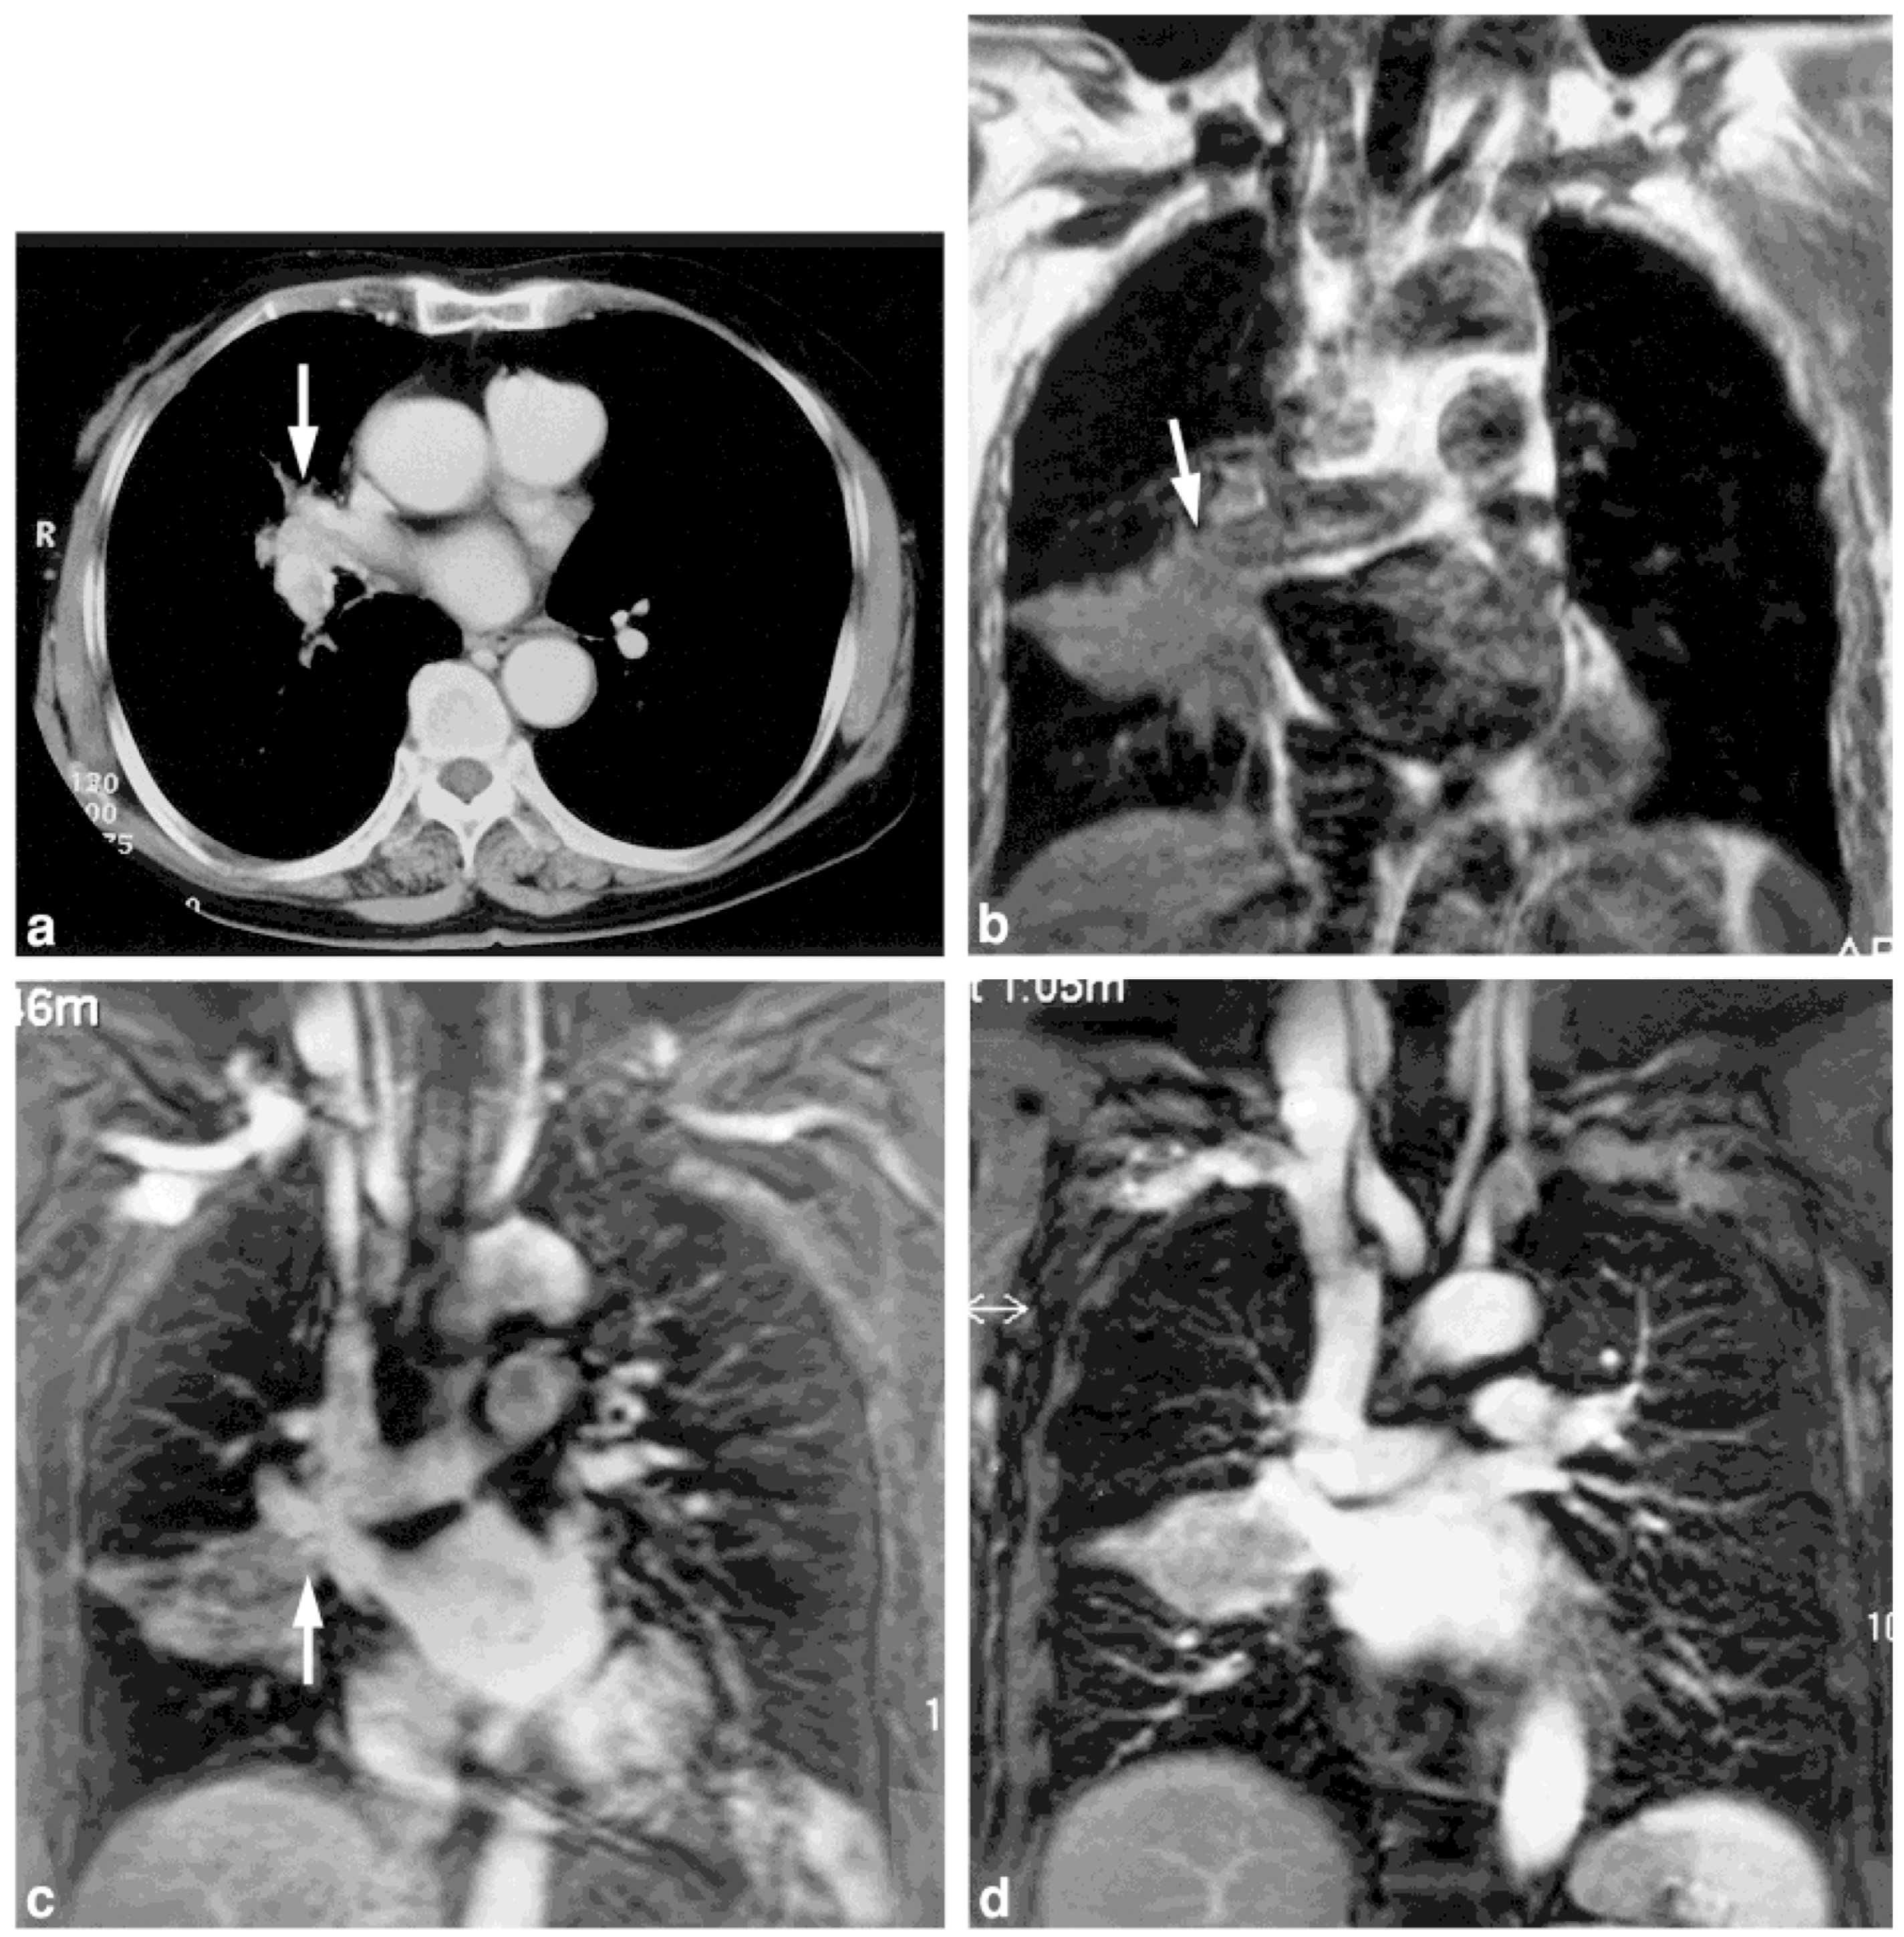

- Ohno, Y.; Adachi, S.; Motoyama, A.; Kusumoto, M.; Hatabu, H.; Sugimura, K.; Kono, M. Multiphase ECG-triggered 3D contrast-enhanced MR angiography: Utility for evaluation of hilar and mediastinal invasion of bronchogenic carcinoma. J. Magn. Reson. Imaging 2001, 13, 215–224. [Google Scholar] [CrossRef] [PubMed]

- Ohno, Y.; Nishio, M.; Koyama, H.; Yoshikawa, T.; Matsumoto, S.; Seki, S.; Sugimura, K. Journal Club: Comparison of assessment of preoperative pulmonary vasculature in patients with non-small cell lung cancer by non-contrast- and 4D contrast-enhanced 3-T MR angiography and contrast-enhanced 64-MDCT. AJR Am. J. Roentgenol. 2014, 202, 493–506. [Google Scholar] [CrossRef] [PubMed]